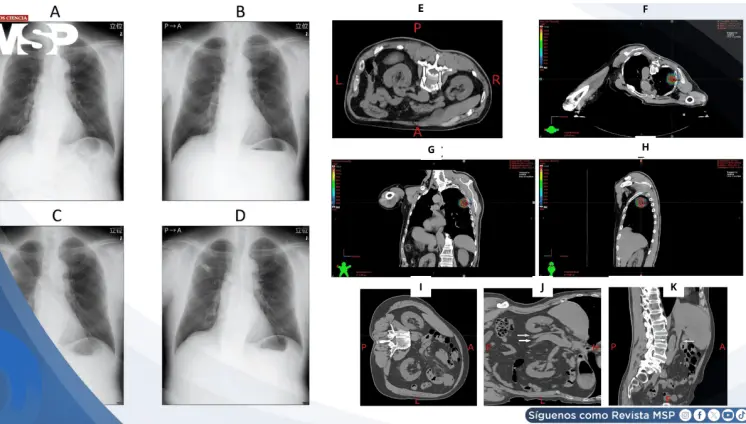

Cálculo vesical gigante adherido a cuerpo extraño rectal desencadenó sepsis fatal en paciente de 60 años

Enero 21, 2026